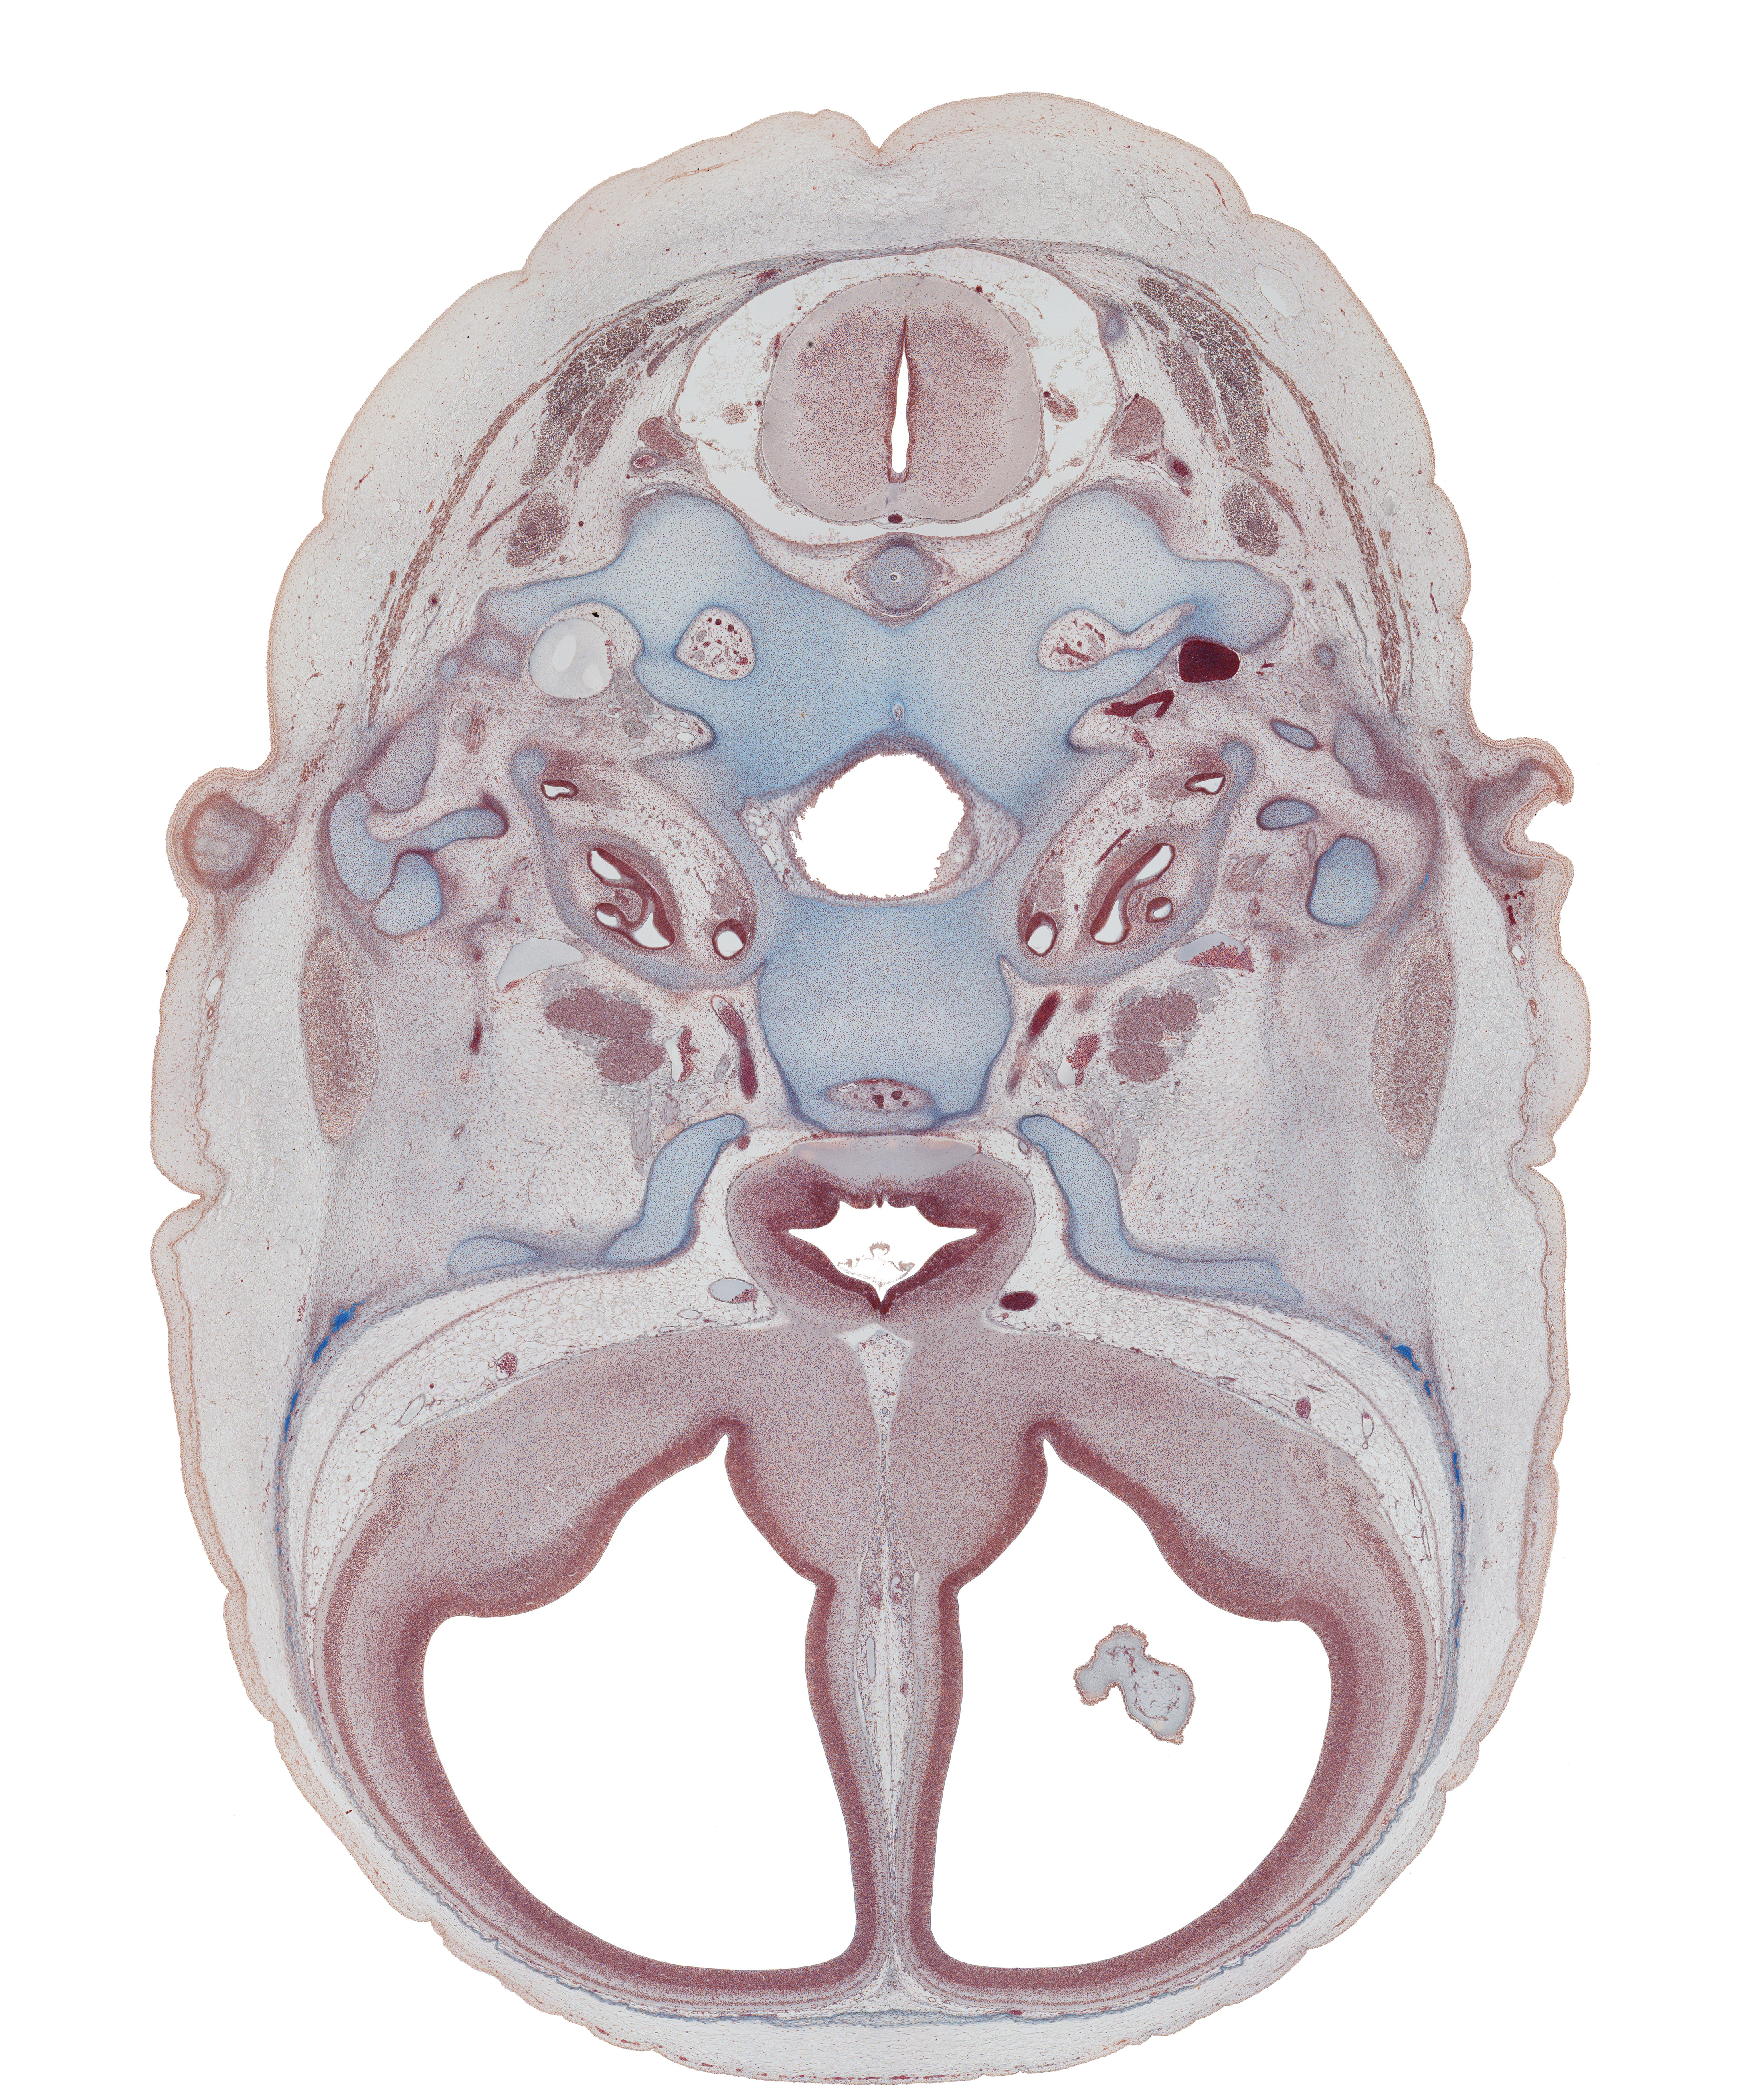

Carnegie Embryo #9226 | Location: 60-01-01

Keywords: C-1 spinal ganglion, anterior spinal artery, basi-occipital (basal plate), central canal, cochlear duct, cranial cavity, edge of choroid plexus, hypoglossal canal, hypophysial fossa, incus, intermediate zone, internal carotid artery, internal jugular vein, lamina terminalis, lesser wing of sphenoid, malleus, mandibular nerve (CN V₃), marginal zone, nucleus accumbens, ophthalmic nerve (CN V₁), optic chiasma (chiasmatic plate), optic groove, piriform cortex (paleopallium), styloid process, temporalis muscle, tuberculum sellae, ventricular zone

Source: The Virtual Human Embryo.